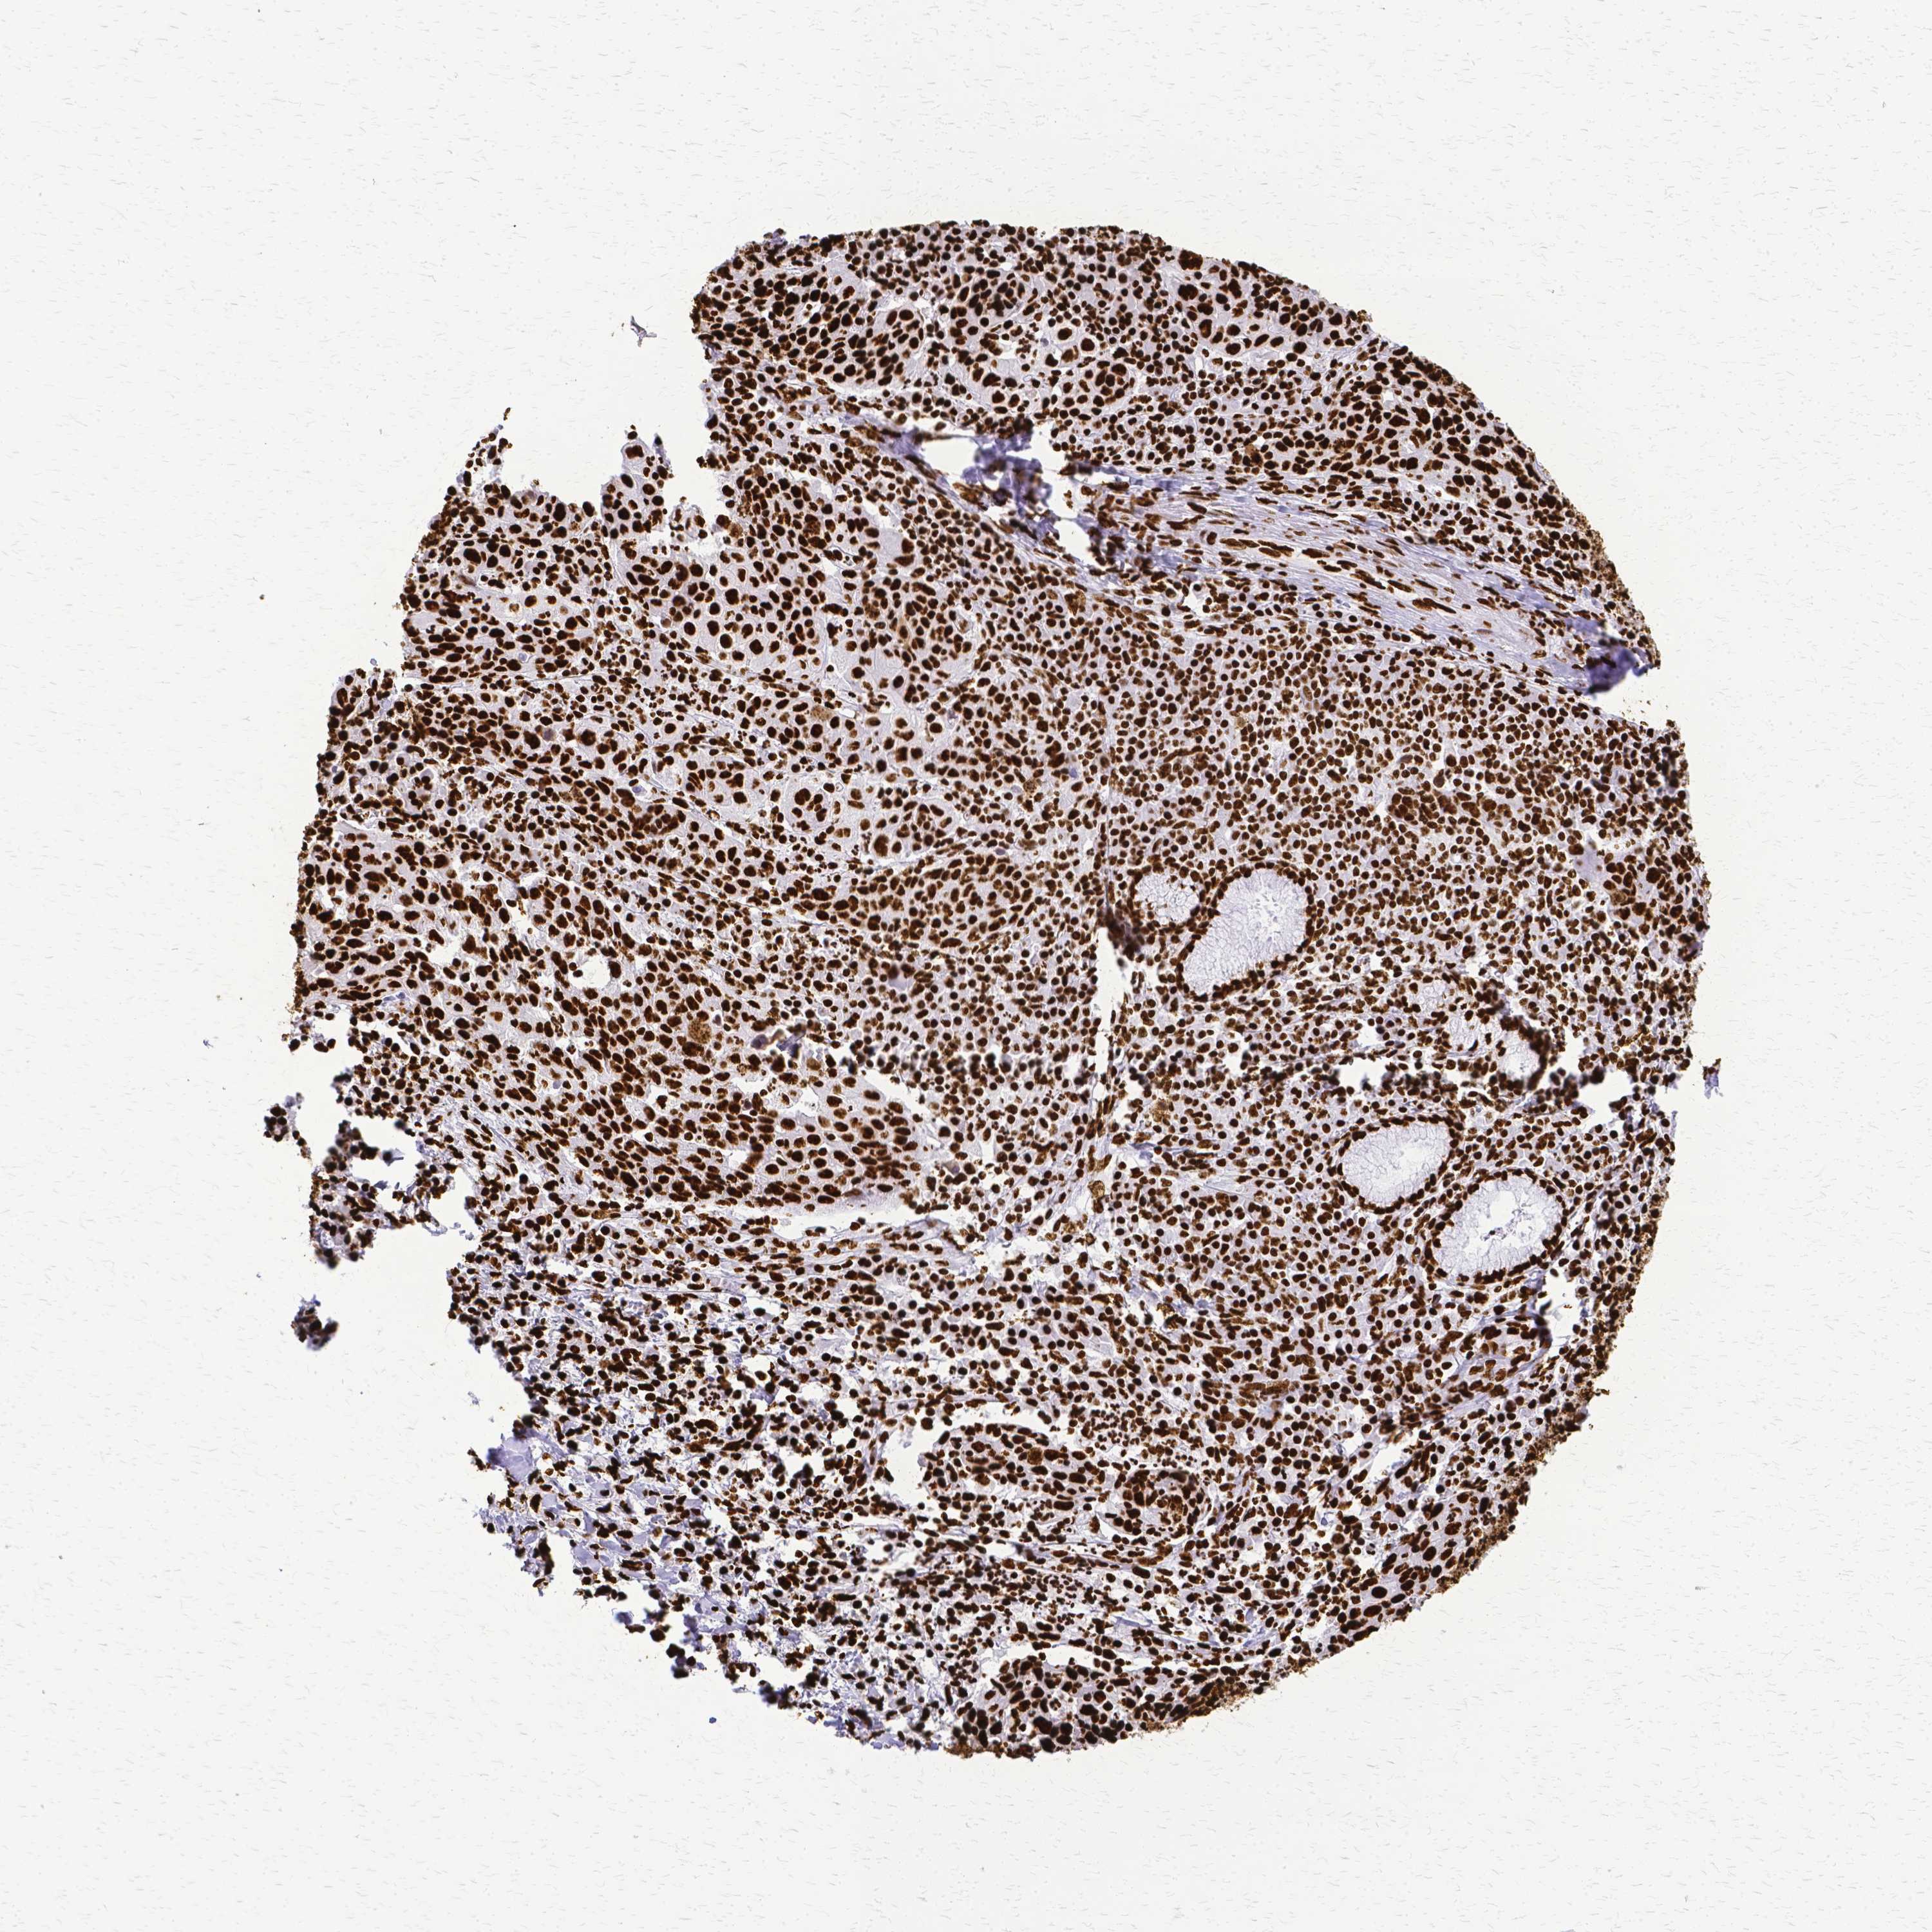

LUNG ADENOCARCINOMA (VALIDATION) - Interactive survival scatter ploti

The Survival Scatter plot shows the clinical status (i.e. dead or alive) for all individuals in the patient cohort, based on the same data that underlies the corresponding Kaplan-Meier plots. Patients that are alive at last time for follow-up are shown in blue and patients who have died during the study are shown in red.

The x-axis shows the expression levels (FPKM) of the investigated gene in the tumor tissue at the time of diagnosis. The y-axis shows the follow-up time after diagnosis (years). Both axes are complimented with kernel density curves demonstrating the data density over the axes. The top density plot shows the expression levels (FPKM) distribution among dead (red) and alive patients (blue). The right density plot shows the data density of the survived years of dead patients with high and low expression levels respectively, stratified using the cutoff indicated by the vertical dashed line through the Survival Scatter plot. This cutoff is automatically defined based on the FPKM cutoff that minimizes the p-score. The cutoff can be changed by dragging the vertical line or by entering a cutoff value in the square labeled "Current cut-off".

Under the Survival Scatter plot the p-score landscape (black curve; left axis) is shown together with dead median separation (red curve; right axis). Dead median separation is the difference in median mRNA expression between patients who have died with high and low expression, respectively. It is calculated as follows: median FPKM expression of dead patients with high expression - median FPKM expression of dead patients with low expression. This is intended to aid the user in visually exploring custom cutoffs and the associated p-scores and dead median separation.

Individual patient data is displayed and can be filtered by clicking on one or more of the category buttons on the top of the page. Categories describing expression level and patient information include: high, low, alive, dead, female, male and tumor stages. The scale of the x-axis can be toggled between linear and log-scale by clicking on the "x log" button. Mouse-over function shows TCGA ID, patient information and mRNA expression (FPKM) for each patient.

& Survival analysisi

Kaplan-Meier plots summarize results from analysis of correlation between mRNA expression level and patient survival. Patients were divided based on level of expression into one of the two groups "low" (under cut off) or "high" (over cut off). X-axis shows time for survival (years) and y-axis shows the probability of survival, where 1.0 corresponds to 100 percent.

SFPQ is not prognostic in Lung Adenocarcinoma (validation)

: 73.08

P scorei

N/A

Average pTPM 83.1

Number of samples 105